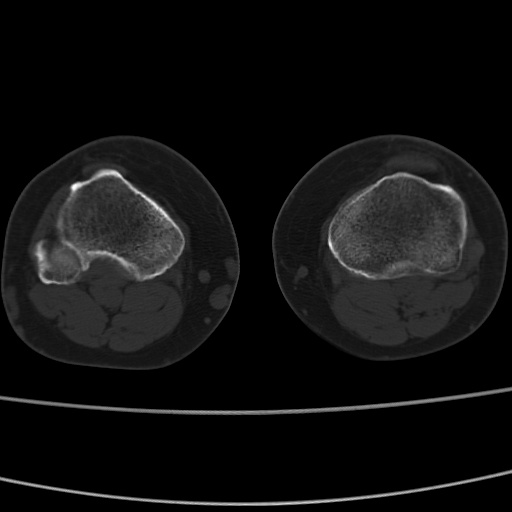

女性,50岁。【请提供患者临床症状体征】

右膝关节退行性改变,关节游离鼠。

右膝关节退行性改变,滑膜黏液囊钙/骨化并游离。

右膝关节退行性改变